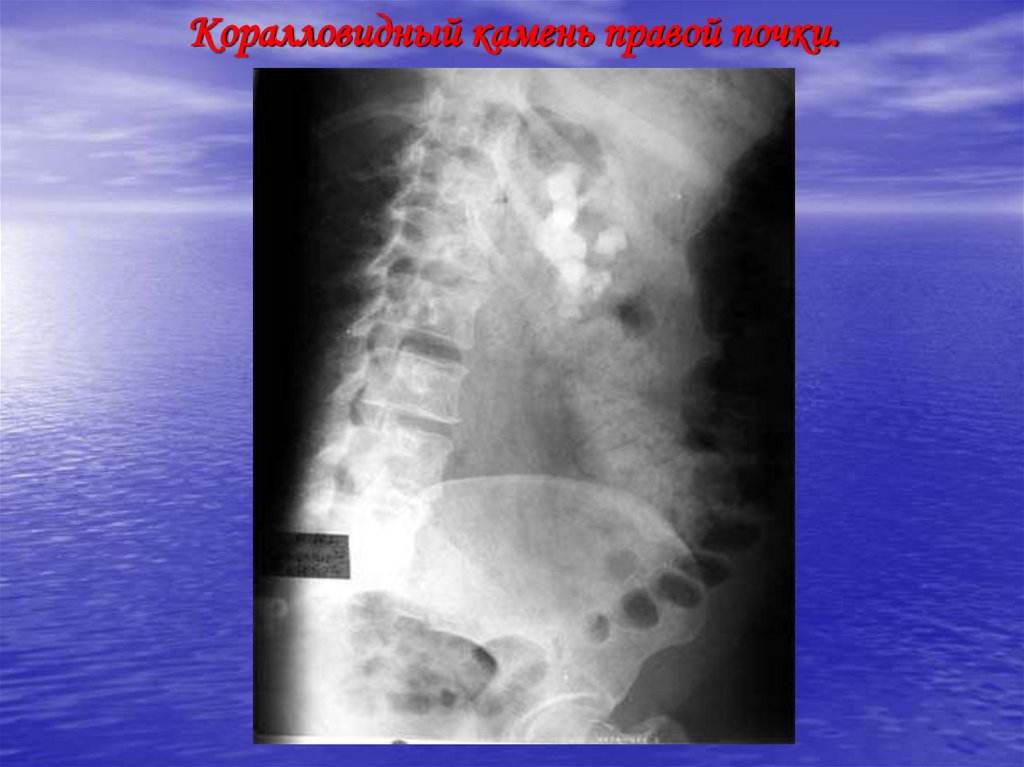

Коралловидный камень правой почки.

42. Коралловидный камень правой почки.

43. Коралловидный камень правой почки.

44. Коралловидный камень правой почки.

45. Коралловидный камень правой почки.